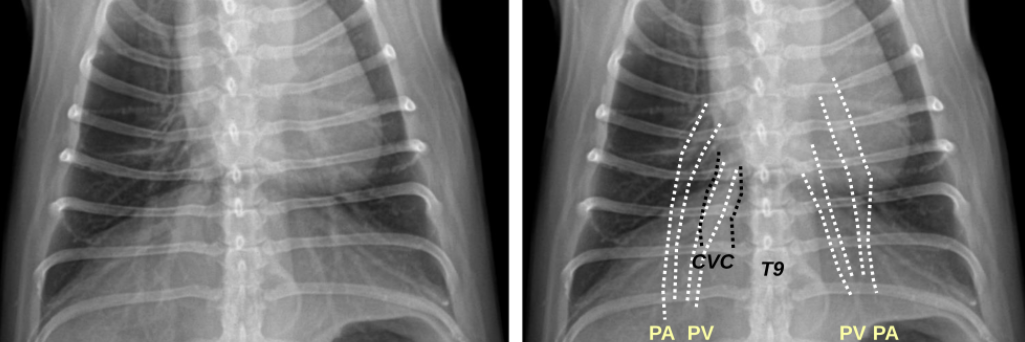

1. Normal Anatomy

| 정상적인 공기의 흐름 : Trachea - Bronchus - Bronchioles - Lung |